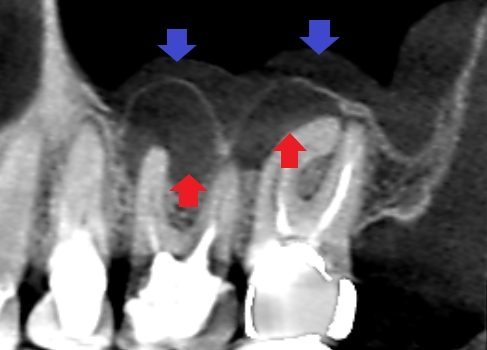

上顎の第一大臼歯と第二大臼歯の初診時のCT画像です。

赤い矢印の先が膿の影です。とても大きく根尖孔外感染という難治性の膿になっている可能性もあります。根の先の膿に隣接して上顎洞内に白い肥厚(青い矢印の先)がみられ、上顎洞炎も同時に起こしています。